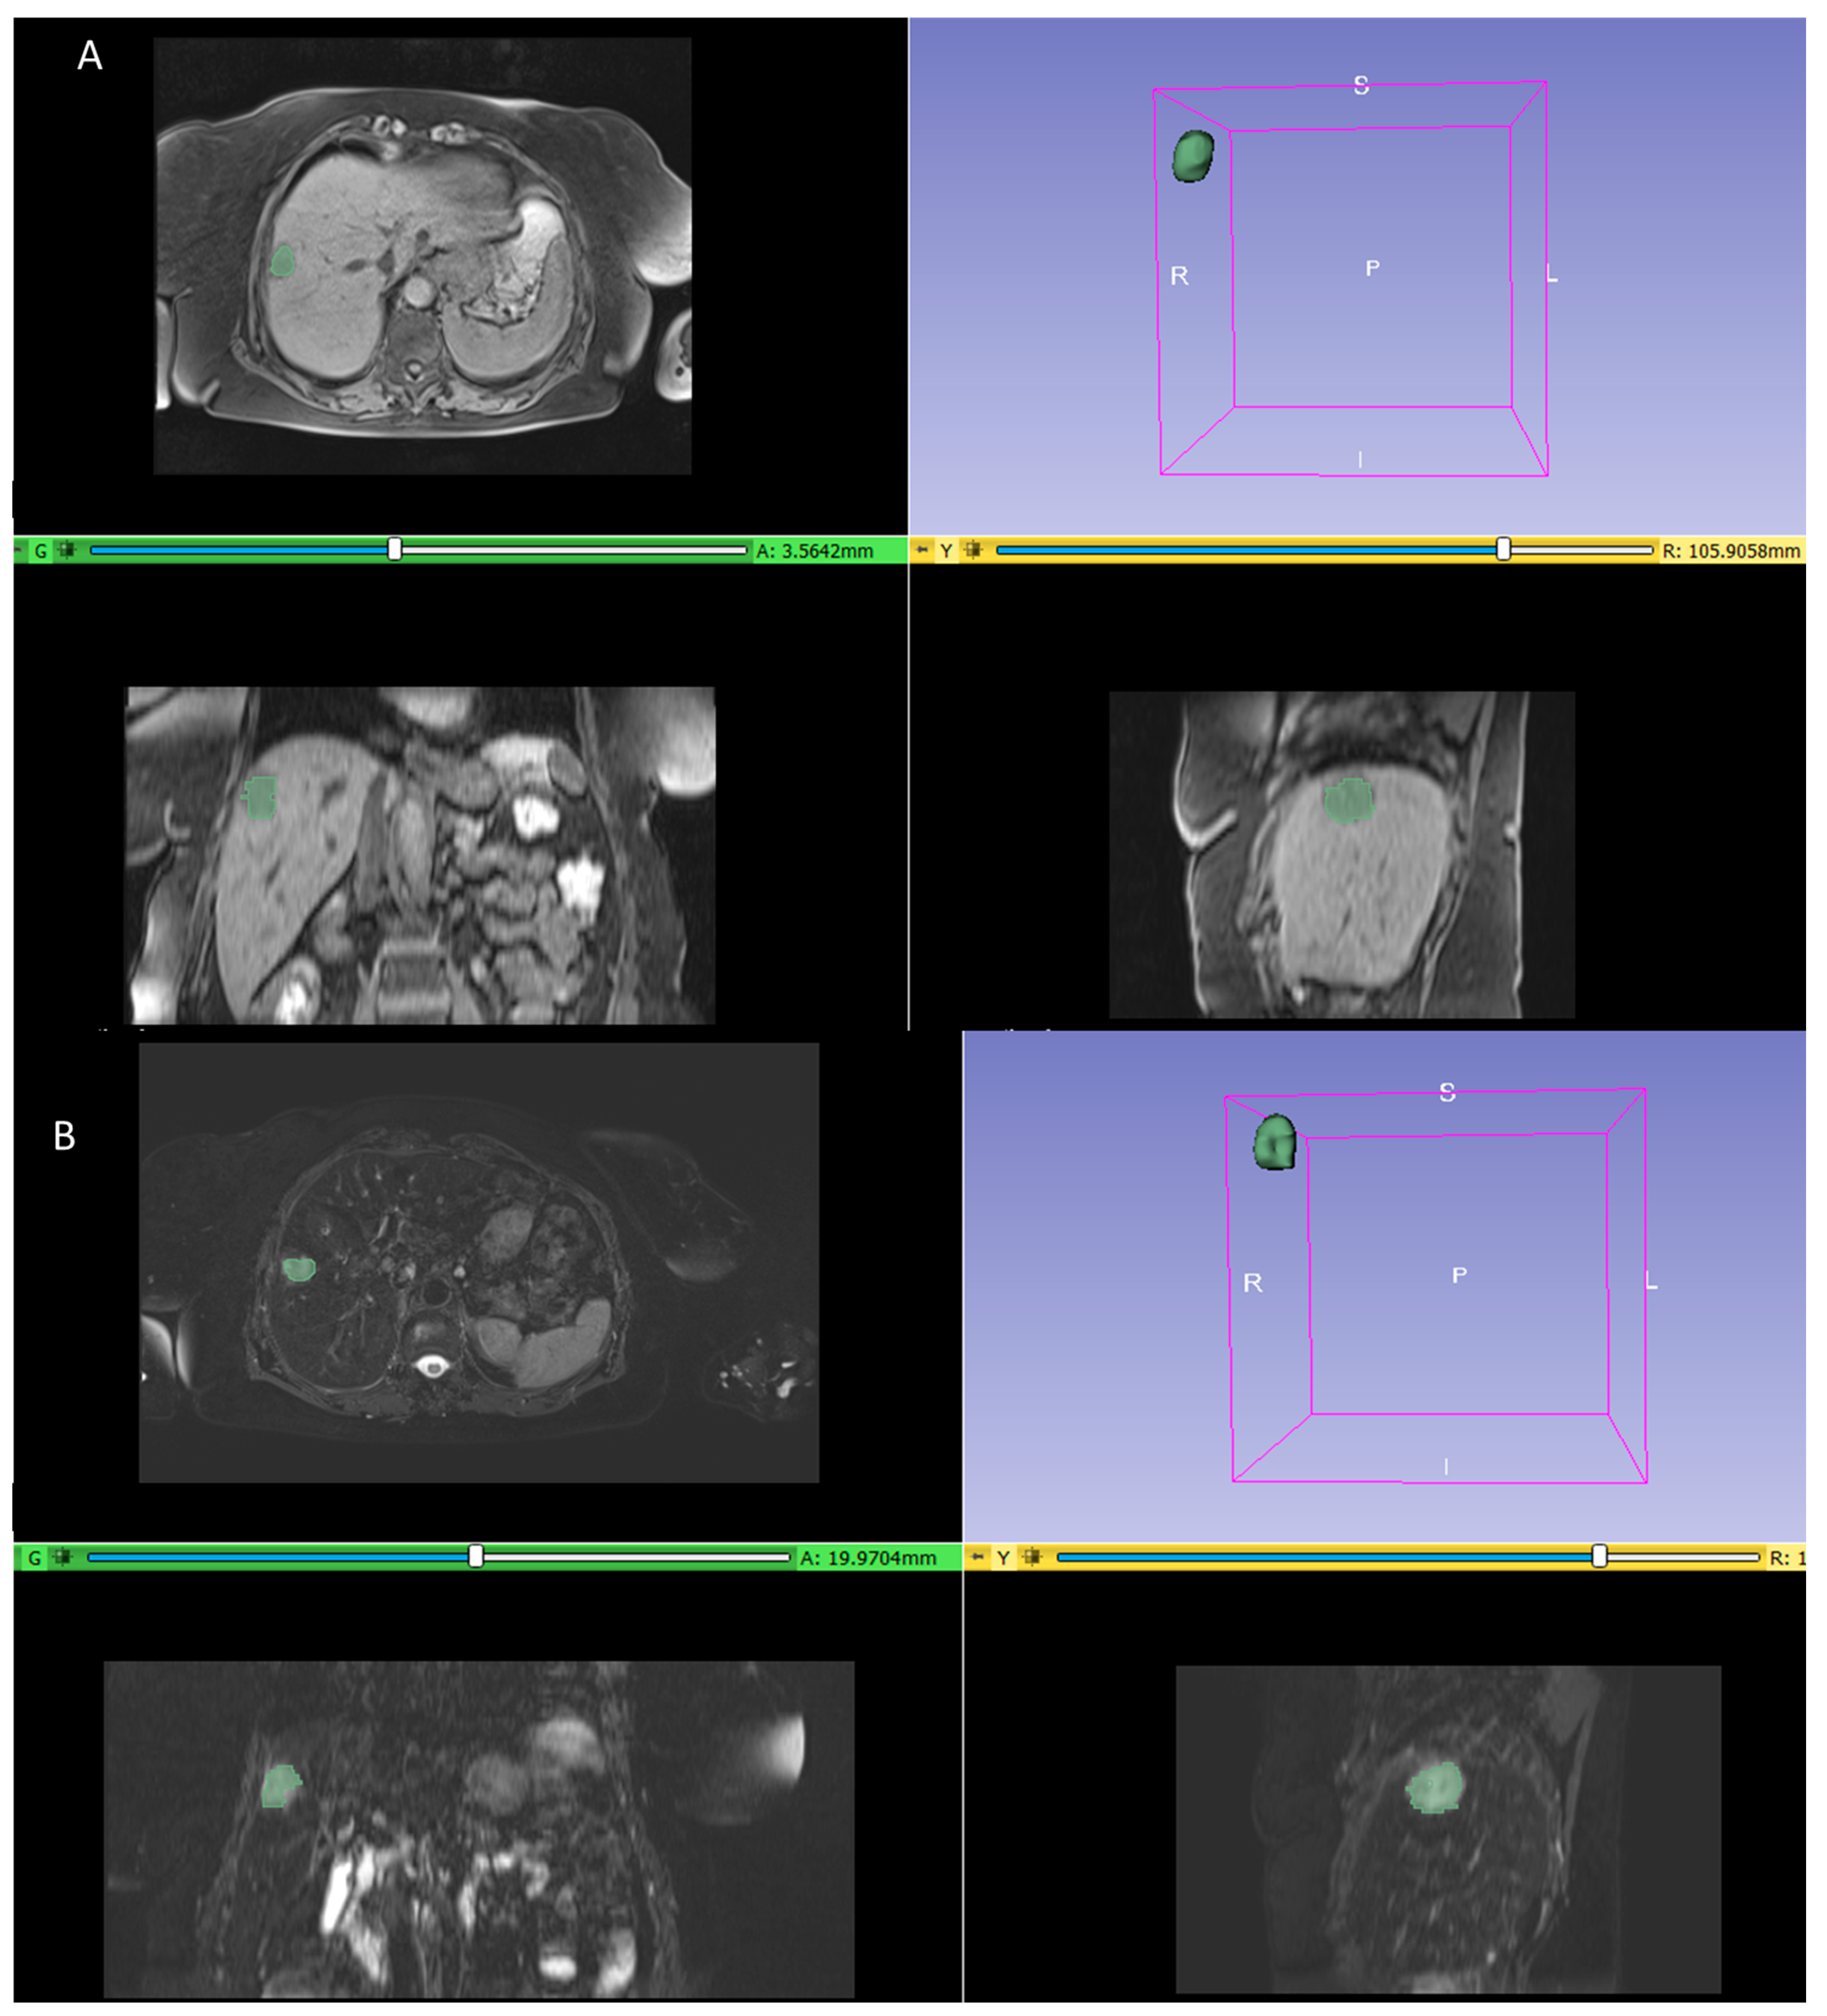

2.2. Imaging

2.3. Image Processing